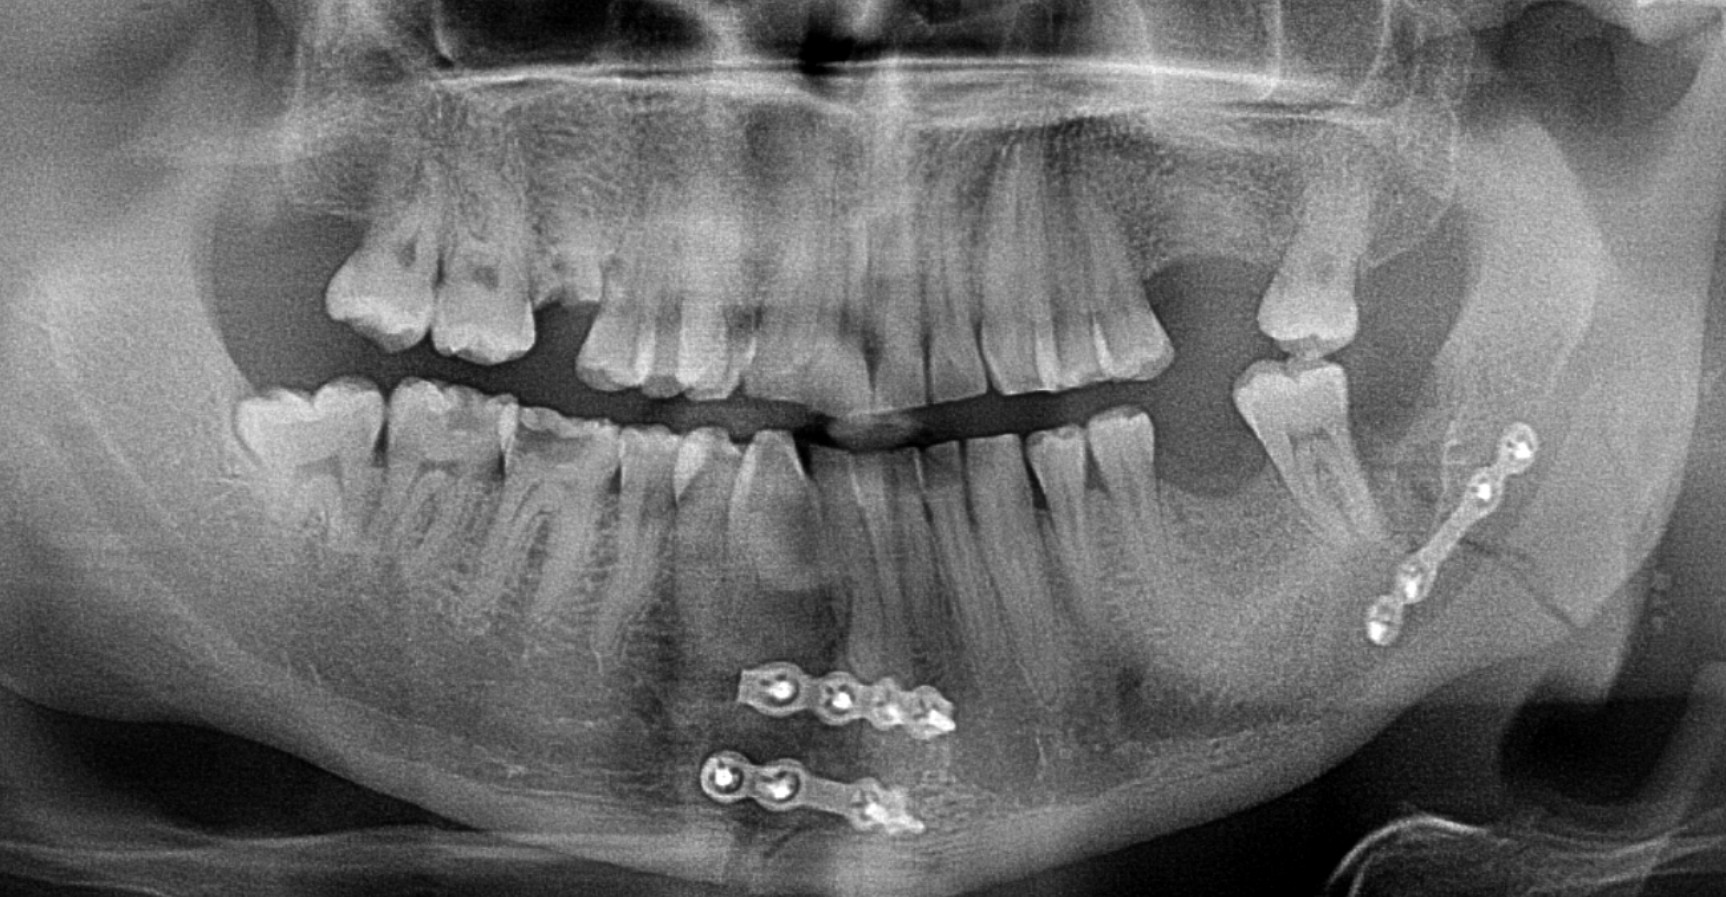

Surgery under general anaesthesia in a hospital is often needed if the bones are displaced, unstable, or affecting important functions like chewing, breathing, or vision. Depending on the type of fracture, surgery will be performed immediately or delayed a few days until swelling settles.

Common surgical treatments include:

- Open Reduction and Internal Fixation (ORIF): The most common procedure, where titanium plates and screws are used to hold the bones in place.

- Jaw wiring: In some jaw fractures, the upper and lower jaws may be temporarily wired together to keep them stable during healing.